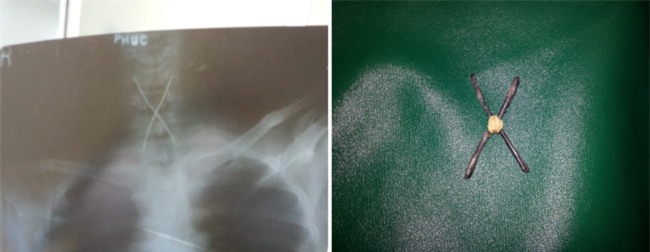

“Bệnh nhân đã chủ động nuốt 2 que sắt nhọn, giấu ở cuống họng để qua mặt lực lượng an ninh. Nhưng không may, que sắt đã đi sâu vào thực quản và mắc kẹt không thể lấy ra được.

Khi được đưa tới bệnh viện cấp cứu, bệnh nhân trong tình trạng nguy kịch.

Ê-kíp trực phải xử lý khẩn cấp để lấy dị vật ra nhằm tránh tổn thương thêm những bộ phận khác”, BS. Phong chia sẻ về một ca nội soi lấy dị vật đặc biệt đã thực hiện.